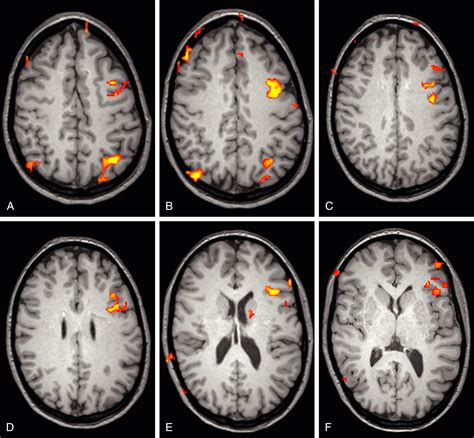

MRI (Magnetic Resonance Imaging) Provides detailed images of the cerebellum, brainstem, and spinal cord to assess the degree of herniation.

💡 Note: MRI remains the gold standard for diagnosing Chiari Type 2, as it provides the necessary contrast to distinguish between nervous tissue and surrounding fluid, allowing neurosurgeons to plan surgical interventions with precision.